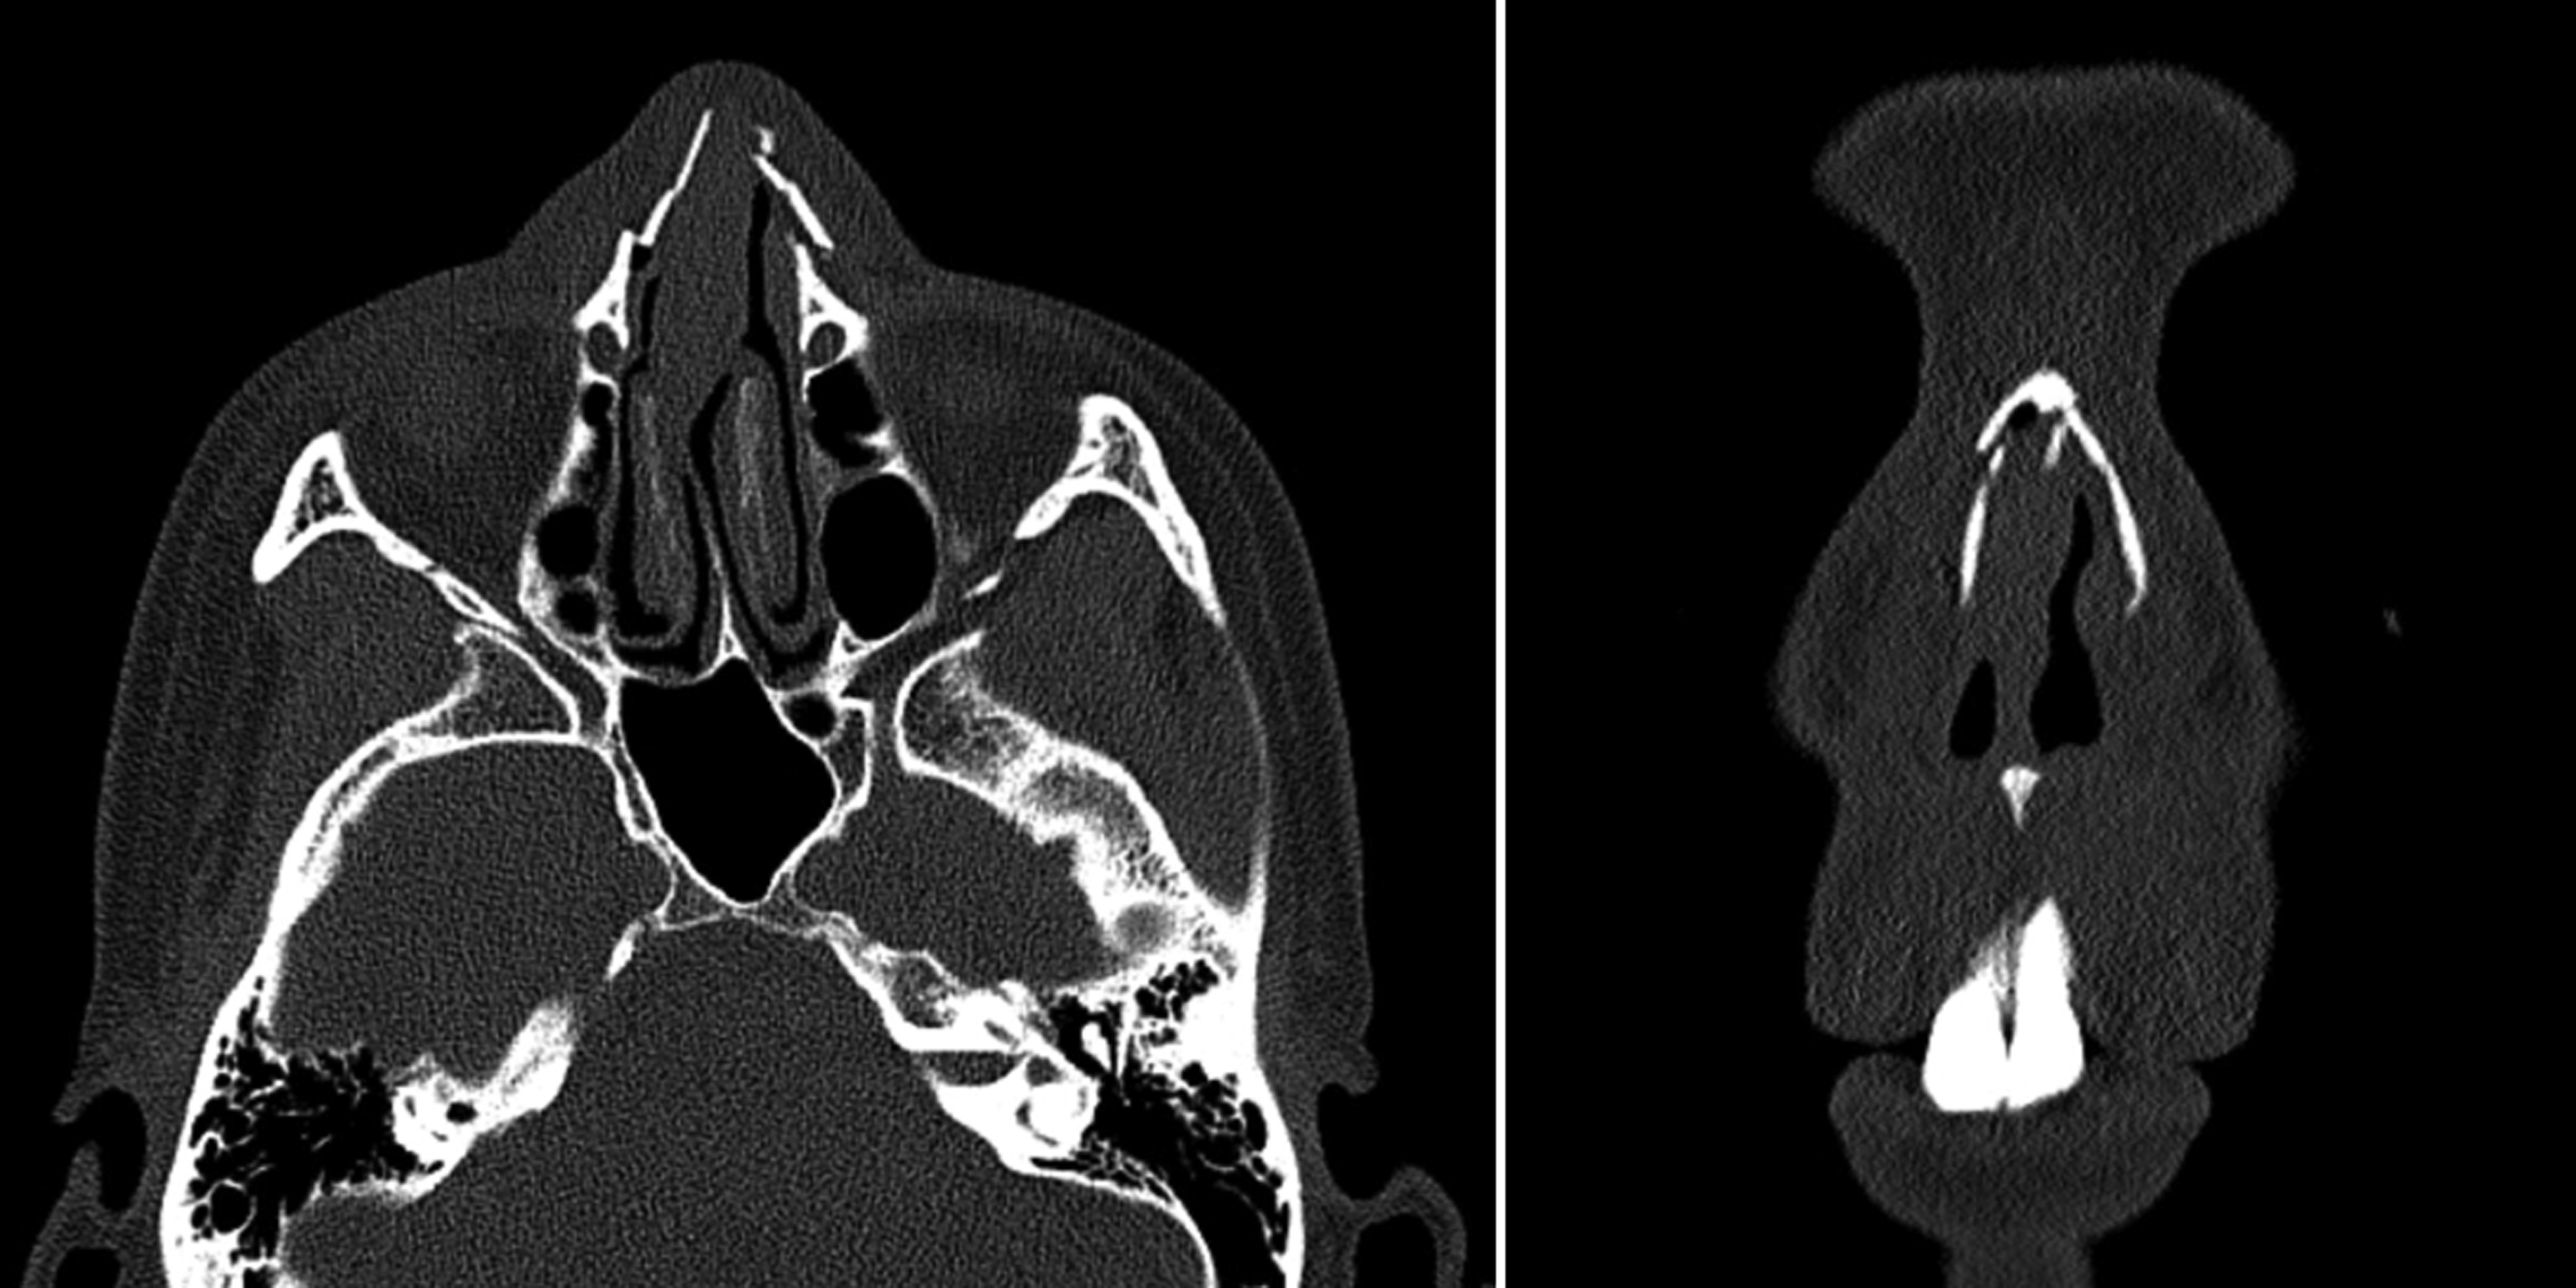

Although not necessarily indicated in isolated nasal bone fractures, imaging is often obtained following facial trauma to evaluate for concurrent maxillofacial bony injury. Depending on the mechanism of trauma, it may be indicated for medicolegal documentation. Lateral plain film radiographs are typically used in the acute care setting. These radiographs may definitively show nasal bone fractures but are limited in their ability to identify nondisplaced nasal bone fractures and septal injury. Noncontrasted computed tomography is much more commonly used in the emergency department setting and evaluates for nasal injury and other facial and head injuries. Although all planes should be evaluated, axial views are often the best way to evaluate for nasal bone fracture, as the axial plane best demonstrates nasal bone displacement, depression, splaying, impaction, and comminution ( Fig. 2 ). Imaging may be deferred in certain settings if there is strong clinical evidence of fracture and no concern for associated injuries, or if there is low suspicion for fracture due to no obvious deformity or nasal obstruction.